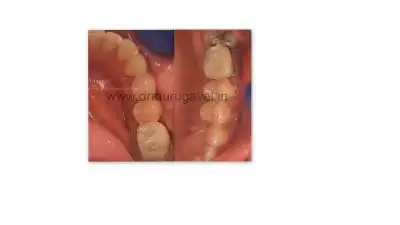

Lower Occlusal View

After treatment :

Digital CAD CAM PMMA Acrylic Crown:

CAD CAM PMMA Acrylic crown was fixed in both upper & lower jaw . Patient started chewing on the same day itself with fixed teeth & felt happy & enjoying his food on both sides.